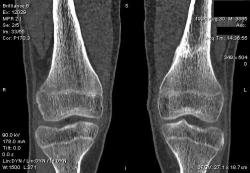

Мальчик 15 лет. Несколько месяцев назад начали беспокоить боли в коленных суставах. Травмы не было. Ребёнку был выставлен диагноз: болезнь Шлаттера, назначено лечение. На фоне лечения отмечалось значительное усиление болей, боли локализовались в левом коленном суставе. При дообследовании выявлена следующая рентгенологическая картина. Наши рентгенологи настаивают на срастающемся переломе. Но: 1) перелом без травмы? 2) бедро так не ломается

В голову приходит остеомиелит или опухоль.

Линейный периостит, уже должен был рентгенологов насторожить.

Локальный гиперостоз, выраженный болевой синдром, структура губчатого вещества диафиза не изменена наводит только на остеойд-остеому.

Я бы на первое место поставила патологическую перестройку, так называемый, стрессовый перелом. Мальчик чем-нибудь занимается?

Согласна с Ola-la - рентгенологическая картина более всего соответствует стрессорному перелому, хотя для него характерна локализация в б/берцовой кости. Меня однако, смущает и настораживает клиника - это как раз тот случай, когда я бы не дала 100% гарантии, что так не может манифестировать остеосаркома... Поскольку другие методы (МРТ, сцинтиграфия) вряд ли помогут, я бы взяла пациента на короткое ( 2недели - месяц) динамическое наблюдение.

Да, на мой взгляд, состояние после обычного "травматического перелома" (трещина), не думаю, что имел место "патологический перелом", так как костная ткань "патологически изменена" минимально. "Перистальная реакция"локальная тоже есть, на КТ "локальная  зона склероза" - все это свидетельствует именно об этом. Хотя в памяти у меня хорошо отложился Ваш последний случай о локальном утолщении кортикального слоя, когда "яйца в гнезде" еще не было. То, что анамнестически "травмы не было" - ничего не значит. Вы, по всей видимости, тоже часто встречались с такими случаями, когда ребенок не акцентировал внимание на "травме", как таковой, хотя клиника есть, боль есть. Конечно, рентгенограммы - не дай бог - ни скиалогии, ни структуры.